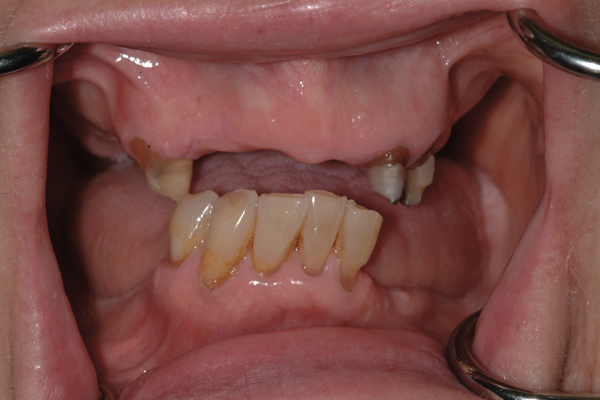

2. Potential “All-on-4” patient with terminal dentition who was unhappy with his smile esthetics.

Figure 2

Fig 18. The patient’s intraoral condition.

Figure 18